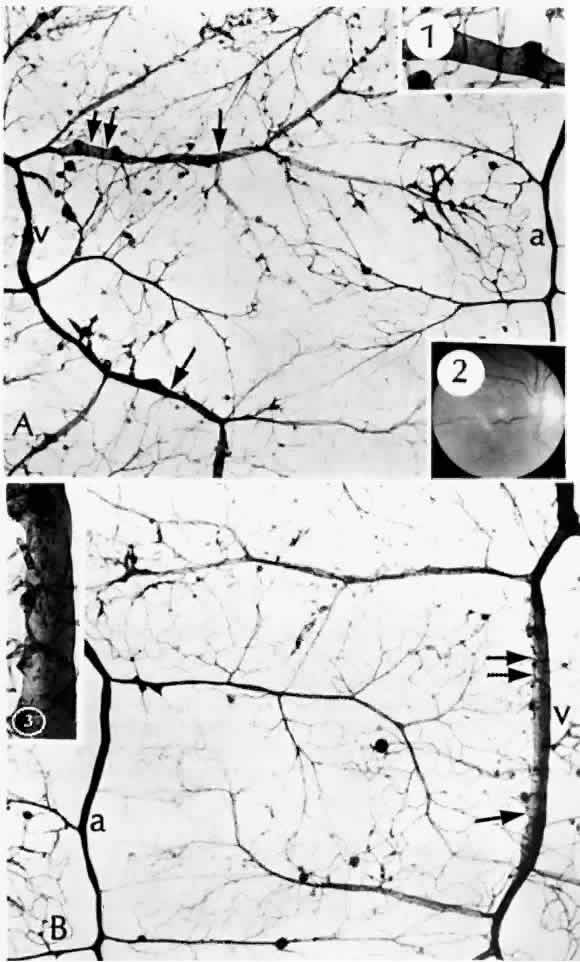

| Diabetic retinopathy can be divided into two types: nonproliferative retinopathy (sometimes called “background” retinopathy) and proliferative retinopathy. “Retinitis proliferans” is an obsolete term for proliferative

surface. In fact, it is not known what prompts the development of diabetic retinopathy, although ischemia clearly plays a role.25 Certain alterations have been observed in blood from diabetic patients, including increased rigidity and aggregation of the erythrocytes, altered platelet activity, changes in plasma proteins, and increased affinity of hemoglobin for oxygen. Both the increased aggregates of platelets and the abnormally rigid erythrocytes can occlude small blood vessels, contributing to retinal ischemia. The increased affinity of hemoglobin for oxygen means that less oxygen is released to the tissues.26 Whether tightly controlling blood sugar levels improves retinopathy or even halts its progression is controversial. In one investigation,27 dogs were made diabetic and put into three groups: good control for 5 years, poor control for 5 years, and poor control for 2½ years followed by good control for the remaining time. The third group had developed almost as many microaneurysms at 5 years as did the group under poor control for the entire time. This study indicates that tight control is maximally beneficial when undertaken early in the course of the disease. Human studies to corroborate or refute this have been understandably difficult to carry out. Transplantation of the pancreas or pancreatic islet cells is one way to normalize blood glucose by restoring endogenous insulin. In one study, eight patients who received pancreatic transplants exhibited no difference in retinopathy between the four whose transplants functioned and the four whose transplants failed.28 In another small study, the proliferative retinopathy of patients who received pancreatic transplants remained stable or worsened, despite their being euglycemic.29 Recently, results from a large prospective series, the Diabetes Control and Complications Trial, have shown that tight control, including three or more daily insulin injections or continuous infusion, based on at least four glucose determinations daily, does prevent development or progression of retinopathy to a significant degree. All patients in the primary prevention group had diabetes for 5 years or less and did not have retinopathy at the outset of the study. Thus, tight control begun early may indeed help prevent or delay the onset of retinopathy.30 As noted previously, duration of disease is a strong predictor for development of retinopathy.31,32 Prepubertal children may develop minimal retinopathy,33 but the blood-retinal barrier is altered during puberty, apparently through hormonal influence, leading to retinopathy.34 Unless the macula is edematous, nonproliferative retinopathy is asymptomatic and may be found only on routine ophthalmoscopy. In patients who develop diabetes after puberty, retinopathy may be a presenting sign of the disease. The earliest manifestation of diabetic retinopathy is the appearance of microaneurysms (Fig. 5, Color Fig. D). They appear as small red dots clinically and often are seen more readily on fluorescein angiography, where they fill and leak, with staining of the vessel wall.35 Histologically they are small “outpouchings” of the capillary vessel wall and are usually saccular but occasionally fusiform in shape. They can occur anywhere along the capillary network between the arteriole and venule.18 Some microaneurysms, however, do not fill with fluorescein and have been shown to be thin-walled capillary outpouchings filled with erythrocytes. They may represent either one stage of microaneurysm formation or a specific type of it.36 As shown by trypsin digestion, capillary pericytes are lost first,27 followed by endothelial cells (Figs. 6 and 7). Aldose reductase, one of the enzymes in the sorbitol metabolic pathway, is present in significant quantities in retinal capillary pericytes, but not in endothelial cells, and may thus be implicated in the formation of microaneurysms.37 The final result is an acellular segment of capillary that is nonperfused on fluorescein angiography.36 The normal retinal vasculature, including the capillaries, forms a barrier to the free exchange of metabolites.38 This blood-retinal barrier is damaged in diabetes, allowing leakage of larger molecules, which are clinically manifested as hard exudates and retinal edema. Ultrastructurally, the normal junctions between capillary endothelial cells are disrupted.39 Hard exudates clinically appear as shiny yellow deposits (see Fig. 5; Color Fig. D). When they surround a microaneurysm in a circular pattern, the condition is called circinate retinopathy. Histologically, the deposits accumulate at the level of the outer plexiform layer (Fig. 8, Color Fig. E) and consist of lipids, complex carbohydrates, and proteins, as demonstrated histochemically. Hard exudates are normally asymptomatic unless they involve the macula, where they cause a drop in visual acuity. If a leaking microaneurysm can be identified on fluorescein angiography, laser photocoagulation can obliterate it. Over time, the fluid is resorbed, and sometimes visual acuity can improve.40 Cystoid macular edema can be caused by many different diseases as well as diabetes. It is characterized by diffuse leakage of the capillaries in the posterior pole. In advanced cases, the cystoid spaces are ophthalmoscopically visible, resembling the petals of a flower. Cystoid edema is seen more easily on fluorescein angiography, since the spaces fill with fluorescein. Histologically, cystoid fluid is seen at the outer plexiform layer, but may also accumulate in the inner nuclear layer. The synapses of the outer plexiform layer are slanted in the fovea because the inner retinal layers are pushed away from the foveal pit. Because of these slanted connections, this area can be distended by fluid more readily. Ultrastructurally, the fluid appears to be located within Müller cells, and there is evidence of capillary endothelial damage.41 In some patients, the cystoid spaces can coalesce, forming lamellar or full-thickness macular holes.42 Other nonproliferative changes include intraretinal hemorrhages. Flame-shaped hemorrhages occur in the nerve fiber layer, and dot-blot hemorrhages occur in deeper retina, in the outer plexiform and inner nuclear layers (Fig. 9). Nonproliferative retinal changes that have been associated statistically with an increased likelihood of development of proliferative retinopathy have sometimes been termed proproliferative retinopathy. These changes indicate an increased level of retinal ischemia. Cotton-wool spots are areas of capillary closure. The ischemic axons swell, with resultant loss of retinal transparency. They occur frequently in diabetics with and without hypertension.43 Clinically, they appear as white, feathery spots, commonly at the bifurcation of retinal vessels. On fluorescein angiography, these areas appear dark, both because of focal capillary closure and nonperfusion, and because the focal retinal swelling obscures the subjacent choroidal fluorescence. Histologically, the axons of the nerve fiber layer are focally swollen in a fusiform configuration and have been called cytoid bodies because the central density superficially resembles a cell with its nucleus.44 Depending on the severity of the ischemia, individual ganglion cells may recover or be lost.20 Capillary dropout in the fovea is an important cause of untreatable visual loss, even if there is no macular edema.43 The foveal avascular zone is significantly larger and more irregular in contour in patients with diabetic retinopathy than in control patients,45 even when the patients have no clinical visual loss.43 The retinal arterioles may become narrowed and irregular. Patients with diabetes are likely to have arteriosclerotic changes in the retina as well as systemically. The arterial wall is thickened, with resultant narrowing of the blood column. Clinically, this narrowing is manifest as a “copper-wire” change and with greater severity, as a “silver-wire” change. These descriptions reflect the narrowed and relatively less visible column of erythrocytes. Even severely narrowed, silver-wire arterioles, however, may still allow some passage of fluorescein. The arterioles may ultimately become occluded,20 and this phenomenon can proceed rapidly, with accompanying capillary dropout.43 Extensive capillary and arteriolar nonperfusion can be even more prominent in the midperipheral retina than posteriorly.46 The retinal veins can also become irregular and tortuous with sausage-shaped dilatations. The vascular walls become diffusely permeable so that they both leak and stain with fluorescein. These changes also seem to be associated with ischemia. As shown by trypsin digestion, the beaded areas are hypercellular (Fig. 10).43 Diabetes is also a risk factor for branch retinal vein occlusion47 and central vein occlusion.43 Other capillary changes, more severe and extensive than microaneurysms, are collectively termed intraretinal microvascular abnormalities (IRMAs). Clinically, these manifest as dilated channels that leak fluorescein and show vascular wall staining (Fig. 11). De Venecia and co-workers36 were able to distinguish between IRMAs arising from arteriolar capillaries and IRMAs arising from venular capillaries. The IRMAs associated with arterioles exhibited early filling and late leakage on angiography. Histologically, they appeared as solid proliferations of endothelial cells, adjacent to acellular capillaries. In some instances, they may represent true intraretinal neovascularization. The IRMAs adjacent to venules filled in the early venous phase and leaked late. Histologically, they were irregularly dilated, had thin walls, and may have represented shunts.

All of these changes are forerunners of proliferative retinopathy. Patients are unlikely to develop proliferative retinopathy before 10 years' duration of diabetes, but thereafter the incidence rises steadily.31,32 Rarely, proliferative retinopathy with vitreal hemorrhage can be the presenting sign in younger patients.48 As in other diseases associated with retinal neovascularization, the stimulus for new vessel formation in diabetes appears to be ischemia. The retina is uniquely dependent on oxygen: its demand on a unit-to-weight basis exceeds that of all other tissues, including the brain.7 A number of growth factors may act on the retina, including somatomedin C (insulin-like growth factor I), platelet-derived endothelial growth factor, fibroblast growth factors, angiogenin, and others.49 According to one recent study of samples of neovascular membranes obtained at vitrectomy from diabetic patients, only vascular endothelial growth factor was present in all specimens.50 This same factor is also present at significantly higher levels in the vitreous in eyes with proliferative retinopathy than in those without the disease.51 The precise role of the different factors in the promotion of neovascularization remains to be elucidated. New vessels that develop on or within a disc diameter of the optic nerve head are termed new vessels at the disc (NVD) (Color Fig. F). Those that develop anywhere else on the retina are called new vessels elsewhere (NVE). NVD indicate a diffuse retinal ischemia, whereas with NVE, the ischemia may be more localized, occurring at a site of previous arteriolar closure or capillary dropout. NVE can occur peripherally as well as in the posterior pole.52 Histologically, new vessels develop between the retinal surface and the posterior surface of the formed vitreous (Fig. 12). With NVE, there is a demonstrable break through the internal limiting membrane (Fig. 13).20 Early-developing new vessels have lumina even at the proliferating tips.53 Active new vessels have endothelial cells and pericytes, with fenestrations. Morphologically, fenestrations are areas ranging from 40 to 80 nm in diameter where the cell membranes are focally fused, and are normal findings in capillaries outside of the retina and brain. They allow increased permeability and are responsible for the diffuse leakage of fluorescein seen from new vessels on angiography. Inactive or “ghost” new vessels are acellular, having lost both endothelium and pericytes.39 With time, fibrous tissue develops and accompanies the new vessels. The vessels themselves may leak and bleed into the vitreous, leading to visual loss. The fibrous tissue is contractile, and has been shown to contain actin filaments.54 Clinically, fibrous proliferation appears as whitish bands on the retinal surface, sometimes obscuring the neovascularization. With retinal elevation, retroretinal membranes also can form. Traction can cause cystoid changes in the retina20 and venous loops,55 as well as retinal detachment (Color Fig. G). Extensive traction can cause macular heterotopia reminiscent of retinopathy of prematurity.56 Histologically, the cells in the membranes appear to be fibrous astrocytes. At least in some cases, however, there is immunohistochemical evidence that cells of Müller can also migrate and form membranes. Intraretinal migration and replacement of outer retinal layers by cells of Müller can appear clinically as retroretinal proliferation.57 Other cells found in preretinal membranes include inflammatory cells (i.e., lymphocytes, plasma cells, and macrophages) and retinal pigment epithelial cells.58 Panretinal photocoagulation, usually accomplished with an argon laser, is used to treat neovascularization of the retina and iris. The Diabetic Retinopathy Study Research Group59 has established the efficacy of this procedure in preventing severe visual loss, a measure that appears to last for at least 15 years.60 Radiant energy in the visible spectrum passes through the transparent retina and is absorbed by melanin pigment, hemoglobin, or both, depending on the wavelength chosen. The result is a focal scar of the outer retina, or if intense enough, full-thickness retina (Fig. 14).61 Full-thickness scars can cause extensive visual field loss because of obliteration of the nerve fiber layer.20 The choriocapillaris is effectively closed by photocoagulation, as demonstrated by studies of vascular casts.62 After panretinal photocoagulation, the oxygen tension on the inner retinal surface is greater over areas of scarring compared with adjacent areas of intact retina, presumably due in part to greater oxygen diffusion from the larger vessels of the choroid. The increased oxygen levels appear to alleviate retinal ischemia and help explain how photocoagulation causes retinal neovascular regression.63 This finding has been substantiated by direct measurements of oxygen tension in human patients undergoing vitrectomy.64 In the juxtafoveal area, krypton red was associated with less inner retinal damage than argon green.65,66 This is of clinical importance in the treatment of macular edema. The wavelength used, however, appears to be unimportant in extrafoveal areas of the retina.66 Macular grid photocoagulation has been proposed as an effective way to treat macular edema when specific leaking points cannot be identified. In animal studies, this technique appeared to work by occluding some capillaries and reducing the lumen in others, thereby decreasing the ratio of the retinal capillary area to the retinal area. The photoreceptors and retinal pigment epithelium were initially damaged but later recovered.67 |